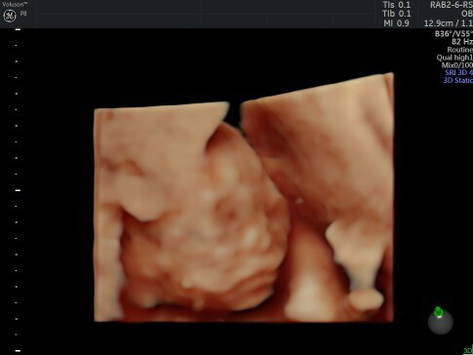

masyaallahh tabarokallah.. sudah msuk 19 minggu 6 hari. kedutan masih halus pas usg ternyata aktif banget. sampe pas video manyun manyun lagi ngempeng juga dd nya.. sayangnya JK msh ketutupan betis jd belum bisa dpastikan takutnya meleset kata dokter. bunda bunda yg HPL september 2021 udh ngerasain apa aja.?? #bantusharing #firstbaby #1stimemom sharing yuk